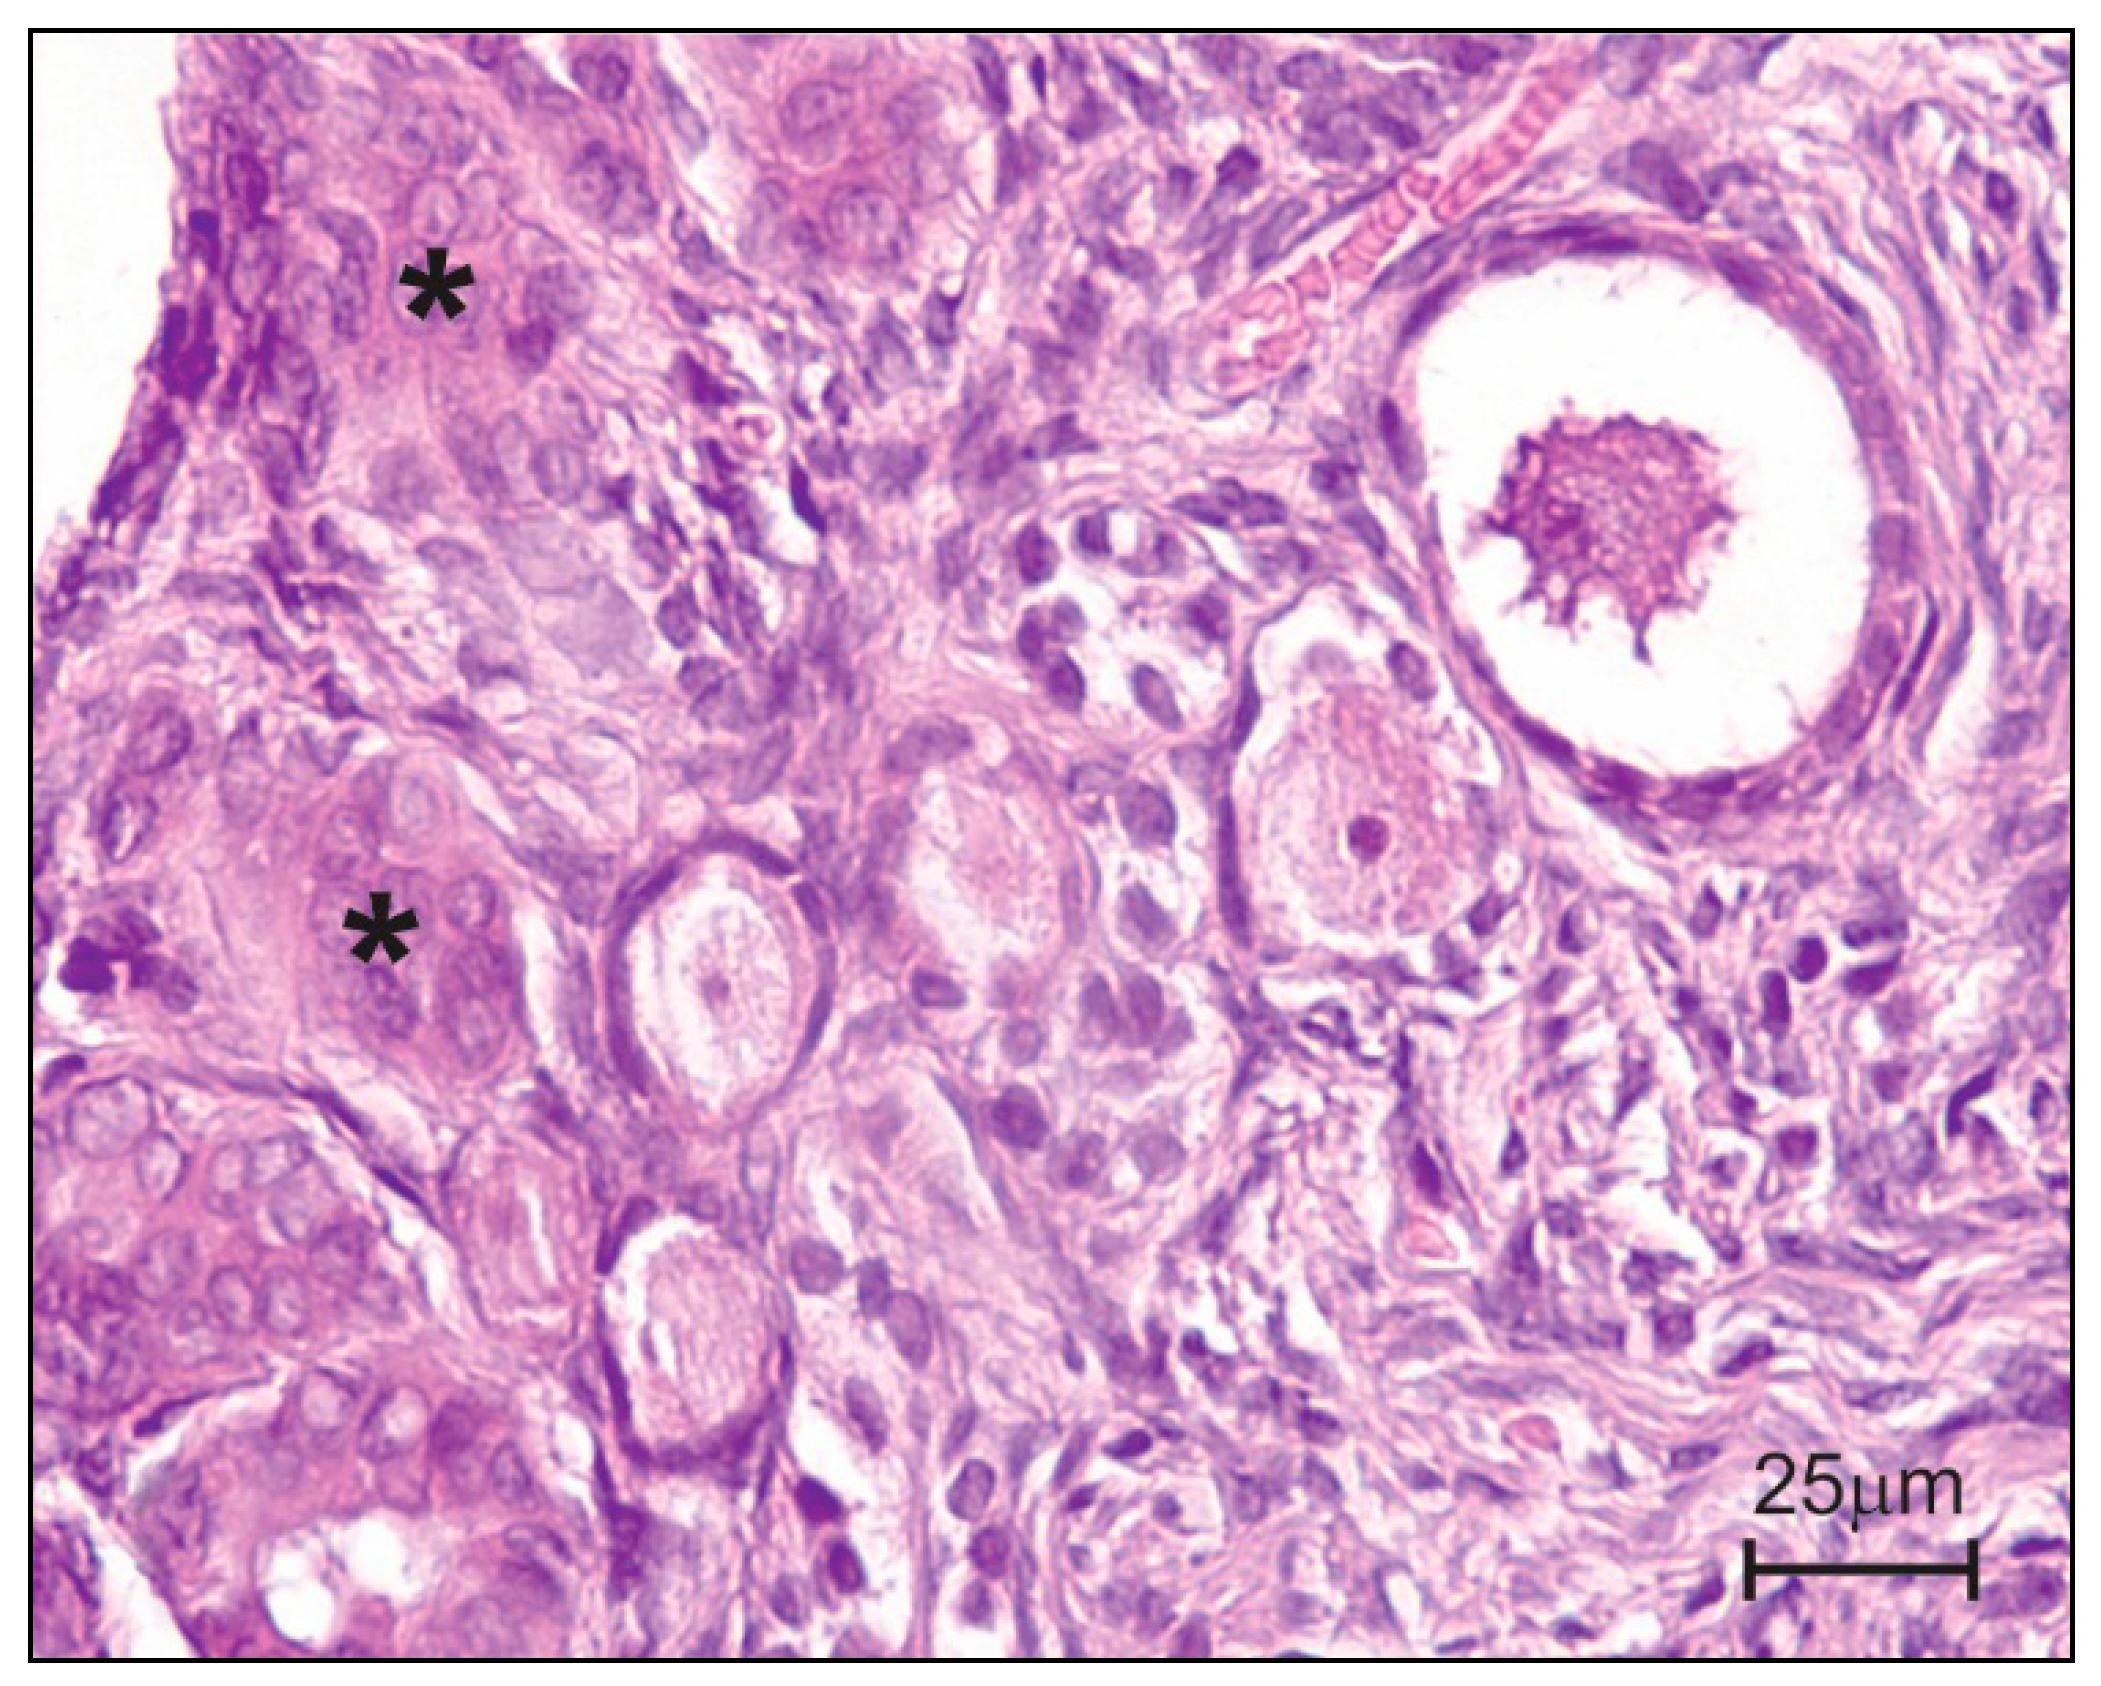

- Gajęcka, M.; Obremski, K.; Jakimiuk, E.; Skorska-Wyszyńska, E.; Zielonka, Ł.; Gajęcki, M. Histopathological examination of ovaries in bitches after experimental zearalenone micotoxicosis. Pol. J. Vet. Sci. 2008, 11, 363–366. [Google Scholar] [PubMed]

- Gajęcka, M. The effects of experimental administration of low doses of zearalenone on the histology of ovaries in pre pubertal bitches. Pol. J. Vet. Sci. 2013, 16, 313–322. [Google Scholar] [PubMed]

- Gajęcka, M. The effect of experimental low zearalenone intoxication on ovarian follicles in pre-pubertal bitches. Pol. J. Vet. Sci. 2013, 16, 45–54. [Google Scholar] [CrossRef] [PubMed]